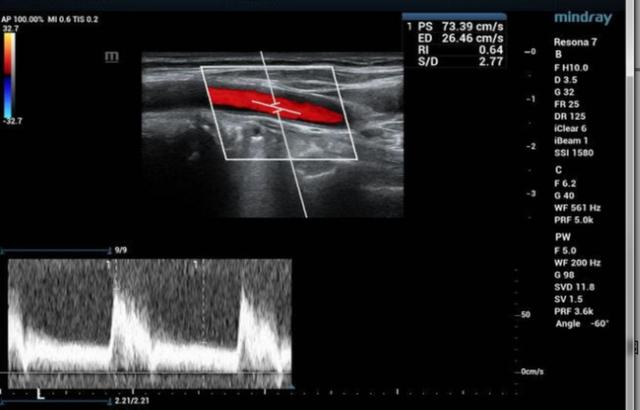

颈动脉B超

如果想知道自己有没有发生冠心病的可能性,最简单方便的项目是颈动脉B超,可以观察有无动脉粥样硬化、血管狭窄,当颈动脉发现有动脉粥样硬化斑块时,往往提示同为动脉的冠状动脉也有可能存在斑块及血管狭窄的情况。